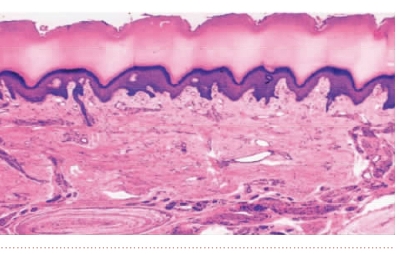

皮肤是人体最大的器官,由表皮和真皮组成,借皮下组织与深部的组织相连(图11-4-1)。皮肤内有表皮衍生的毛、指(趾)甲、汗腺、皮脂腺等皮肤附属器,还有丰富的神经和血管。皮肤具有重要的屏障作用,并能调节体温、感受外界的多种刺激。

图11-4-1 皮肤(手掌皮)光镜图